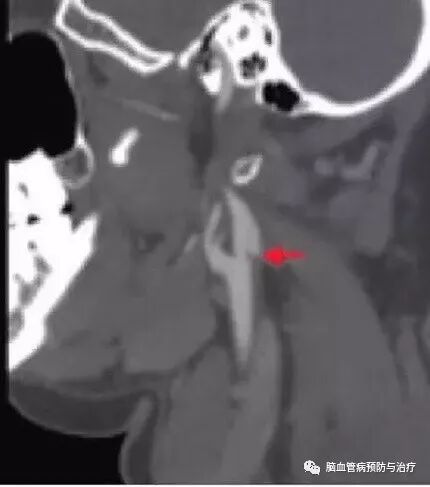

颈动脉蹼的特征非常显著,与“蹼”这个名词相关,只是这里发生在颈动脉,而非手指与脚趾,通过影像学检查而获得明确诊断非常容易。彩超上可见颈动脉管腔狭窄或漂浮的薄膜,CTA轴位表现为薄层隔膜,矢状切面表现为沿着颈动脉球后壁腔内薄层充盈缺损,超过颈动脉分叉处;DSA显示最清晰,颈内动脉后壁薄膜样突起、造影剂排空延迟。